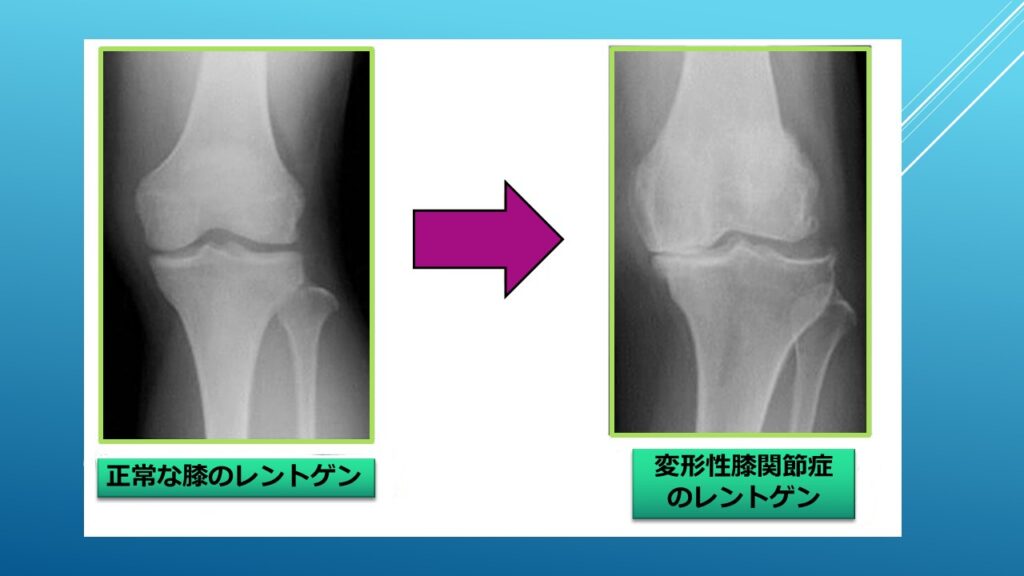

膝の骨の間には、クッションの役割を果たす「軟骨」があります。軟骨自体には神経が通っていないため、少しすり減っただけでは痛みを感じません。では、なぜ痛むのでしょうか?

それは、長年の使用や体重の負荷でこの軟骨がすり減ると、軟骨の削りカスが関節を包む「滑膜(かつまく)」という組織を刺激し、炎症を起こすからです。いわば、関節の中で「小さな火事」が起きている状態です。

これが、整形外科で最も多い「変形性膝関節症」による痛みの正体です。